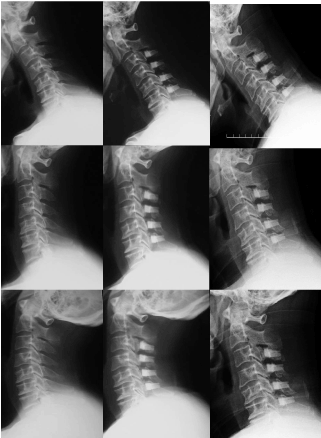

Figure 2. Plain radiographs 4 year after first operation showed obvious limitation of motion in C2-7 angle(0°) and exaggerated flexion at the C7/T1 segment (upper; flexion, center; neutral, lower; extension, left; preoperation, ROM28°, center; 1 year after first operation, ROM18°, right; 4 year after operation, ROM0°)